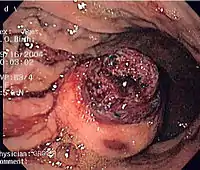

Диагностика

Биоптат исследуется под микроскопом для выявления особенностей ГИСО (веретеноклеточный вариант — 70—80 %, эпителиодный — 20—30 %). Опухоли небольших размеров обычно могут быть ограничены мышечным слоем стенки органа. Крупные опухоли обычно растут, преимущественно кнаружи, из стенки органа, пока их объём не превысит их кровоснабжение, после чего в толще опухоли развивается некротическая полость, которая может в конечном счёте сформировать соустье с полостью органа.

При подозрении на ГИСО, в отличие от схожих опухолей, патолог может использовать иммуногистохимический метод с применением специфических меченых антител, окрашивающих молекулу CD117 (c-kit). 95 % всех ГИСО CD117-позитивны (в числе других возможных маркёров — CD34, DOG-1, десмин и виментин). Тучные клетки также являются CD117-позитивными.

В случае отрицательного результата окраски CD117 и сохраняющихся подозрениях на ГИСО может использоваться новое антитело DOG-1. Также для подтверждения диагноза может применяться секвенирование KIT и PDGFRA.

Небольшие ГИСО

Так как ГИСО происходят из мышечного слоя (который располагается глубже слизистого и подслизистого слоёв), небольшие ГИСО чаще визуализируются как подслизистое или внутристеночное объёмное образование. При исследовании желудочно-кишечного тракта с барием обычно выявляются ровные контуры образования, формирующие прямой или тупой угол со стенкой, что наблюдается и при любых других интрамуральных процессах. Поверхность слизистой интактна, за исключением случаев изъязвления, которые присутствуют при 50 % ГИСО. При КТ с контрастным усилением, небольшие ГИСО обычно визуализируются как интрамуральные образования с ровными, чёткими контурами и гомогенным контрастированием.